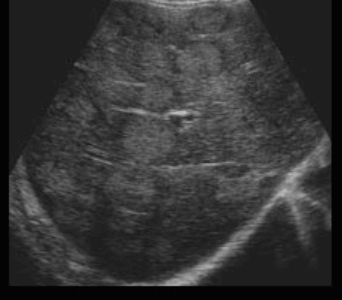

US finding

- 동일한 크기의 다발성 종괴가 나타난다.

- 고에코의 다발성 종괴: 대장암이 많으나 위암도 비교적 흔하다.

- 저에코의 다발성 종괴: 유방암, 폐암등에서 나타난다.

- 석회화나 내부 낭성 변성은 전이성 간종양을 시사하는 소견이다.

- bull's eys sign (종양 변연에 중심부가 고에코이고 경계부가 저에코인 두꺼운 띠가 보인다)

- cluster sign (종양이 융합하여 분엽모양을 이루어 마치 포도송이 모양을 나타낸다)